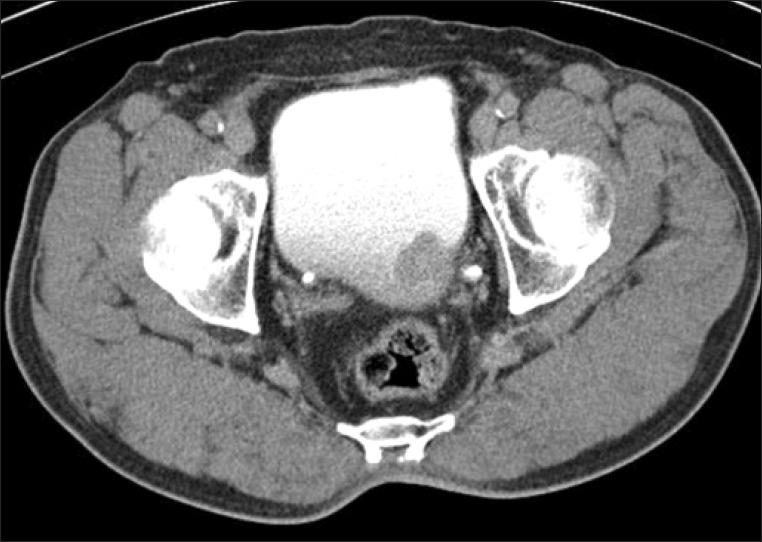

A 71-year-old man was referred for painless hematuria and a bladder tumor. Cystoscopy and computed tomography revealed a 3-cm oval nodular mass on the left lateral side of the bladder. The patient underwent a complete transurethral resection of the lesion and histology showed a proliferation of atypical spindle cells with inflammation consistent with a myofibroblastic tumor. After 4 and 7 months, follow-up cystoscopy demonstrated nodular mass lesions and transurethral resection of bladder tumor was done, which showed chronic cystitis and a recurred myofibroblastic tumor, respectively. Five months later, multiple lymph node, bone, and soft tissue metastases were found by positron emission tomography. The patient was treated first with palliative chemotherapy, including doxorubicin and cisplatin. After that, radiologic studies showed disease progression but the patient refused further treatment and died 6 months later.

一名71岁男性因无痛性血尿和膀胱肿瘤前来就诊。膀胱镜检查和计算机断层扫描显示膀胱左侧有一个3厘米的椭圆形结节状肿块。患者接受了病变的完全经尿道切除术,组织学检查显示非典型梭形细胞增生并伴有炎症,符合肌成纤维细胞瘤。4个月和7个月后,随访膀胱镜检查发现结节状肿块病变,分别进行了膀胱肿瘤经尿道切除术,结果显示为慢性膀胱炎和复发性肌成纤维细胞瘤。5个月后,正电子发射断层扫描发现多处淋巴结、骨骼和软组织转移。患者首先接受了姑息化疗,包括阿霉素和顺铂。此后,影像学研究显示疾病进展,但患者拒绝进一步治疗,6个月后死亡。